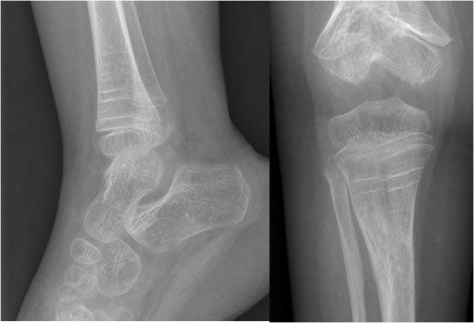

SIGNO DE LA BANDA METAFISARIA DENSA

Aumento de densidad de las metáfisis (flecha) visible en la radiografías convencionales, no acompañado de aplanamiento o deformidad del hueso. Corresponde a una rápida deposición de calcio en las metáfisis que acontece después de varias circunstancias en las que se compromete la osteogénesis. El resultado es el aumento del número y grosor de las trabéculas óseas en las metáfisis.

Este signo puede verse como variante de la normalidad, en las intoxicaciones por plomo u otros metales pesados, en la leucemia tratada, en el hipotiroidismo congénito, en el hiperparatiroidismo y en infecciones transplacentarias (toxoplasmosis, rubéola, citomegalovirus, herpes).

Referencia: Raber SA. The dense metaphyseal band sign. Radiology 1999; 211: 773-774.